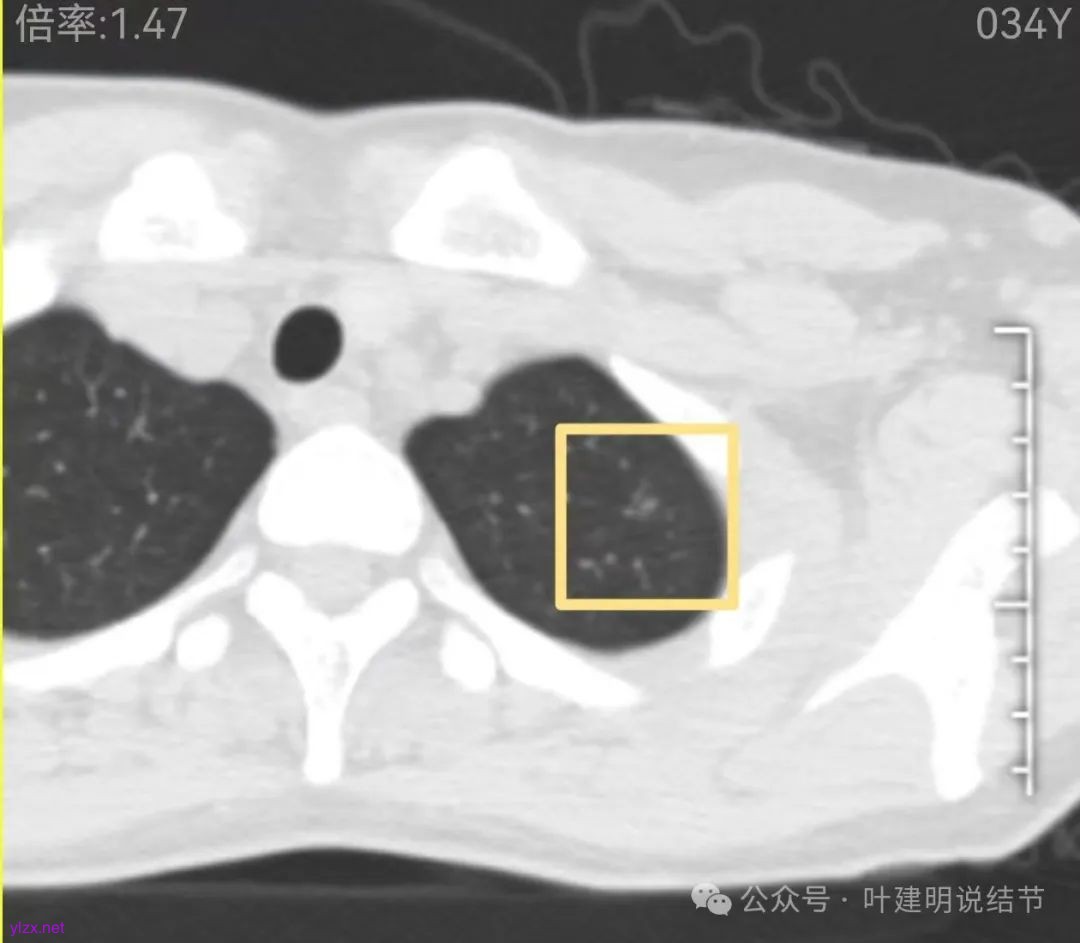

两肺多发结节,左侧黄色标注的考虑是肺泡上皮增生可能性大;蓝色的考虑肺泡上皮增生或者少许慢性炎可能性大;右侧红色宽起来并带有红色箭头的这处是主病灶,偏混合密度,整体轮廓较为清楚,边缘显得毛糙,从2024年12月份的来看,要考虑是肿瘤范畴,原位癌或者微浸润性腺癌可能性较大,也不能完全排除不典型增生。但是在2022年的时候,这个病灶的边上也有一个实性的微小结节,如果只看2022年的,这么小的实性结节,又比较圆,表面也显得较为光滑,是要考虑良性的,当然太小了需要动态观察。回头再重新来看2024年底的,发现绿色箭头所指的这个微小实性的较2022年几乎没有变,去仔细寻找2022年的,发现当时在实性结节旁边也有密度很淡的一点磨玻璃影(也可能真的就是一处,只是扫描不够薄,密度的变化有些突兀而已),而到了2024年12月份,实性微小这处没有明显变化,但是原来很淡的磨玻璃变成了混合磨玻璃,范围也明显扩大。所以总体来看右肺下叶这处是考虑恶性的,而且从磨玻璃结节角度来讲,还是生长比较快的,就是说还是有一定风险的。加上左侧还有两处也是磨玻璃持续存在,虽然边缘轮廓显模糊一点,但多年以后也可能仍然要变成原位癌或者微浸润性腺癌之类的东西。通盘考虑以后,我倾向于右侧近期单孔胸腔镜下微创局部切除,左侧随访观察,等到有进展并风险增加再来考虑处理。意见供参考!